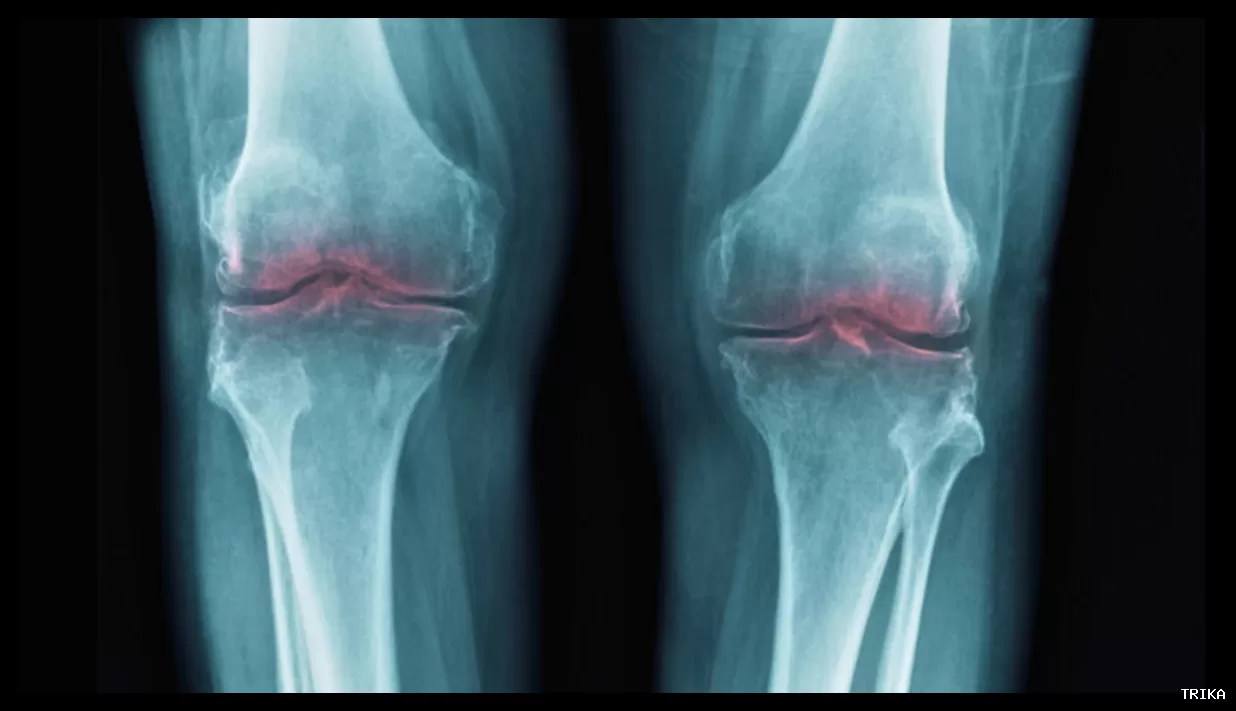

آرتروز یک بیماری شایع تحلیلبرنده مفاصل است که باعث درد، خشکی، تورم و کاهش دامنه حرکتی میشود. این عارضه معمولاً زانوها، لگن و دستها را تحت تأثیر قرار میدهد، اما میتواند سایر مفاصل بدن را نیز درگیر کند. پزشکان معمولاً به مبتلایان به آرتروز توصیه میکنند که ورزش کنند، اما نتایج یک مطالعه جدید نشان میدهد که ورزش ممکن است به اندازهای که قبلاً تصور میشد مفید نباشد.

تیم پژوهشی، اثر ورزش را بر آرتروز در زانو، لگن و دستها بررسی کرده و آن را با گزینههای دیگر شامل عدم مداخله، درمانهای دارونما، آموزش، درمانهای دستی، داروهای مسکن، تزریقها و جراحی مقایسه کرده است. نتایج نشان داد که ورزش به میزان جزئی در کاهش درد در نواحی لگن، زانو و دست تأثیر دارد، اما بهبود عملکردی آن به اندازه دیگر روشها نبوده است.

در مورد آرتروز زانو و لگن، شواهد حاکی از آن است که ورزش در کاهش درد و بهبود عملکرد به اندازه داروهایی مانند ایبوپروفن و کورتیکواستروئیدها مؤثر است. این داروها به طور معمول برای کاهش التهاب در مفاصل تزریق میشوند و حدود ۵ تا ۱۰ درصد درد را کاهش میدهند. پژوهشگران نتیجهگیری کردند که ورزش در بهبود درد و عملکرد، نسبت به تعویض کامل مفصل اثر کمتری دارد.